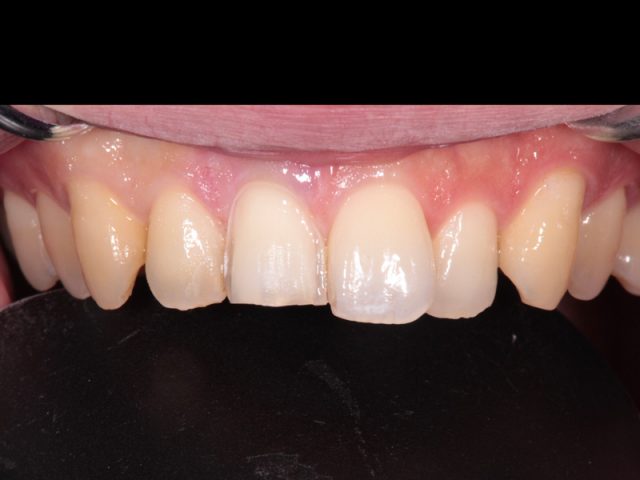

Before

After

| 診断名 | ラミネートベニア(2本) |

|---|---|

| 年齢・性別 | 30代・男性 |

| 治療期間・回数 | 2週間~3週間/2回 |

| 治療方法 | ラミネートべニアで審美修復 |

| 費用 | 1歯 132,000(税込み) |

| デメリット・注意点 | 保険が適用できないため自費診療になる。 セラミックスインレー・クラウンに強い力がかかると割れてしまう恐れがあるため、歯ぎしりや食いしばりが癖になっている患者様にはおすすめできない場合がある |